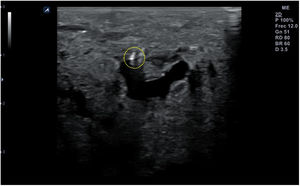

Técnica de exploraciónLa exploración ecográfica se realiza con sonda lineal de alta frecuencia (7,5-12MHz). Se debe hacer de forma estandarizada en las distintas áreas anatómicas, que permita identificar los diferentes tejidos, tanto normales como patológicos, observados en reposo y en movimiento. Los signos ecográficos patológicos habituales son la colección hipo- o anecoica comprimible y desplazable en recesos articulares en los derrames (fig. 10), el engrosamiento hipo- o anecoico del tejido en una vaina sinovial con o sin líquido en la tenosinovitis (fig. 11), la interrupción y espiculación de la línea cortical en las erosiones óseas (fig. 12), la aparición de material ecogénico en el espacio sinovial o articular en las sinovitis y el pannus respectivamente, y la presencia de señal doppler en los procesos con inflamación activa (fig. 13). Deben identificarse en 2 planos distintos para evitar la confusión por la presencia habitual de artefactos. Se ha de aplicar gel suficiente que permita el contacto de toda la superficie de la sonda con la piel, evitando el aire entre ambos, y se debe ejercer una presión firme pero no excesiva, que impida colapsar los neovasos visibles mediante el doppler. Estos serán más fáciles de encontrar con la articulación en flexoextensión fisiológica.

La punción se puede hacer en el eje largo de la sonda, denominada también «en plano» (fig. 14), con la aguja entre 30 y 45° de inclinación respecto a la superficie, lo que permite visualizarla en todo su trayecto, y lo hace muy recomendable cuando haya riesgo de lesionar estructuras cercanas. La aguja aparecerá en la pantalla como una línea hiperecogénica brillante con artefacto de reverberación (al ser un objeto metálico, se dibujarán líneas paralelas hiperecogénicas por debajo de la misma por un efecto espejo). Para poder visualizar correctamente todo el trayecto de la aguja, esta debe orientarse en el mismo plano de corte de la sonda.